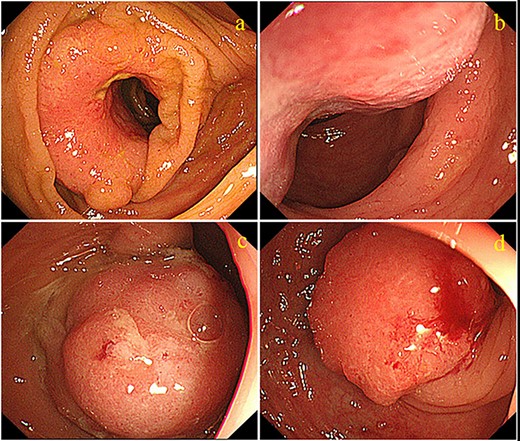

A 70-year-old man who was positive for a blood stool test visited our hospital. Colonoscopy, computed tomography (CT) and barium enema indicated quadruple concurrent locally advanced cancers. The first tumor, with observed lumen stenosis, was located in the ascending colon; the second tumor was located in the descending colon and the third and fourth tumors were located in the sigmoid colon (Fig. 1). CT revealed marked intestinal wall thickness in the ascending, descending and sigmoid colon (Fig. 2). Preoperative precise simulation using 3D angiography was performed to determine adequate lymph node dissection along the arteries feeding the tumors and appropriate resection to avoid anastomotic leakages.

Colonoscopy images showing four tumors. (a) One cauliflower-like tumor with lumen stenosis is located in the ascending colon. (b) Another cauliflower-like tumor is located in the descending colon. The third (c) and fourth (d) tumors are located in the sigmoid colon.